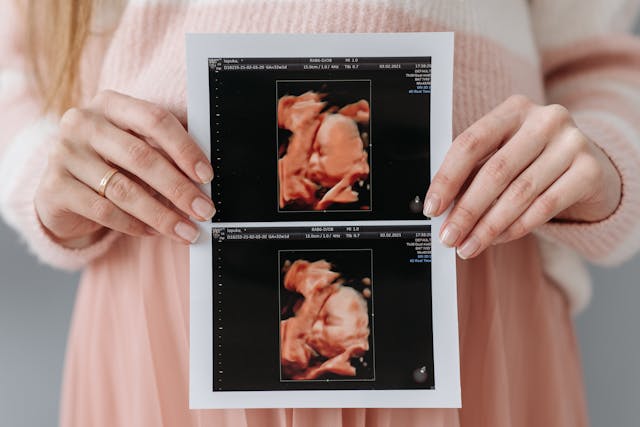

¿Quieres conocer cómo se está desarrollando tu bebé? La ecografía fetal es la solución perfecta para ti. Esta avanzada técnica médica utiliza ultrasonidos para garantizar el normal crecimiento fetal y detectar posibles anomalías. Con el avance de la tecnología, las ecografías 3D y 4D brindan imágenes más detalladas, permitiendo una mejor interpretación y un diagnóstico prenatal de alta precisión, ofreciéndote una visión clara del bienestar de tu bebé.

La ecografía fetal es un procedimiento médico que utiliza ultrasonidos para examinar el desarrollo del feto y detectar posibles anomalías o problemas durante el embarazo. En las últimas décadas, la tecnología ha avanzado, permitiendo obtener imágenes más detalladas y precisas, como las de las ecografías 3D y 4D.

Se utiliza ultrasonidos para crear imágenes del feto, evaluando su crecimiento y desarrollo. Con las ecografías en 3D y 4D, se obtienen imágenes detalladas del bebé, lo que permite detectar alteraciones físicas, malformaciones o problemas relacionados con la oxigenación o nutrición fetal.

Las ecografías 3D y 4D proporcionan imágenes detalladas de la cara, manos, pies y otras características del feto.

Las imágenes 3D y 4D permiten a los padres ver al bebé de manera más realista y cercana.

La ecografía fetal 3D y 4D es una técnica avanzada que permite visualizar el desarrollo fetal y detectar posibles anomalías durante el embarazo. Estas ecografías ofrecen imágenes detalladas que ayudan a garantizar el bienestar del bebé y de la madre. La Dra. Carolina Luque realiza estos estudios, proporcionando un diagnóstico preciso y entregando las imágenes en formato digital o en papel para que los padres puedan conservar este especial recuerdo.